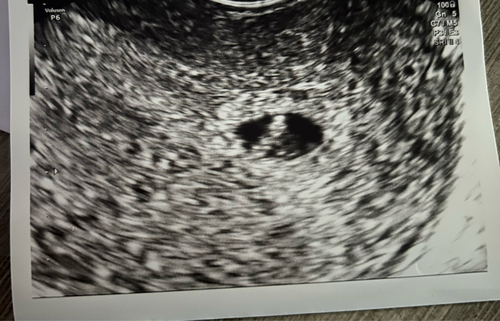

Bij mij is de vruchtzak ook wat aan de kleine kant!

Ze hebben vandaag niet gemeten, maar zag er een beetje uit zoals op jouw foto. Mogen dinsdagavond weer kijken, veel te spannend dit